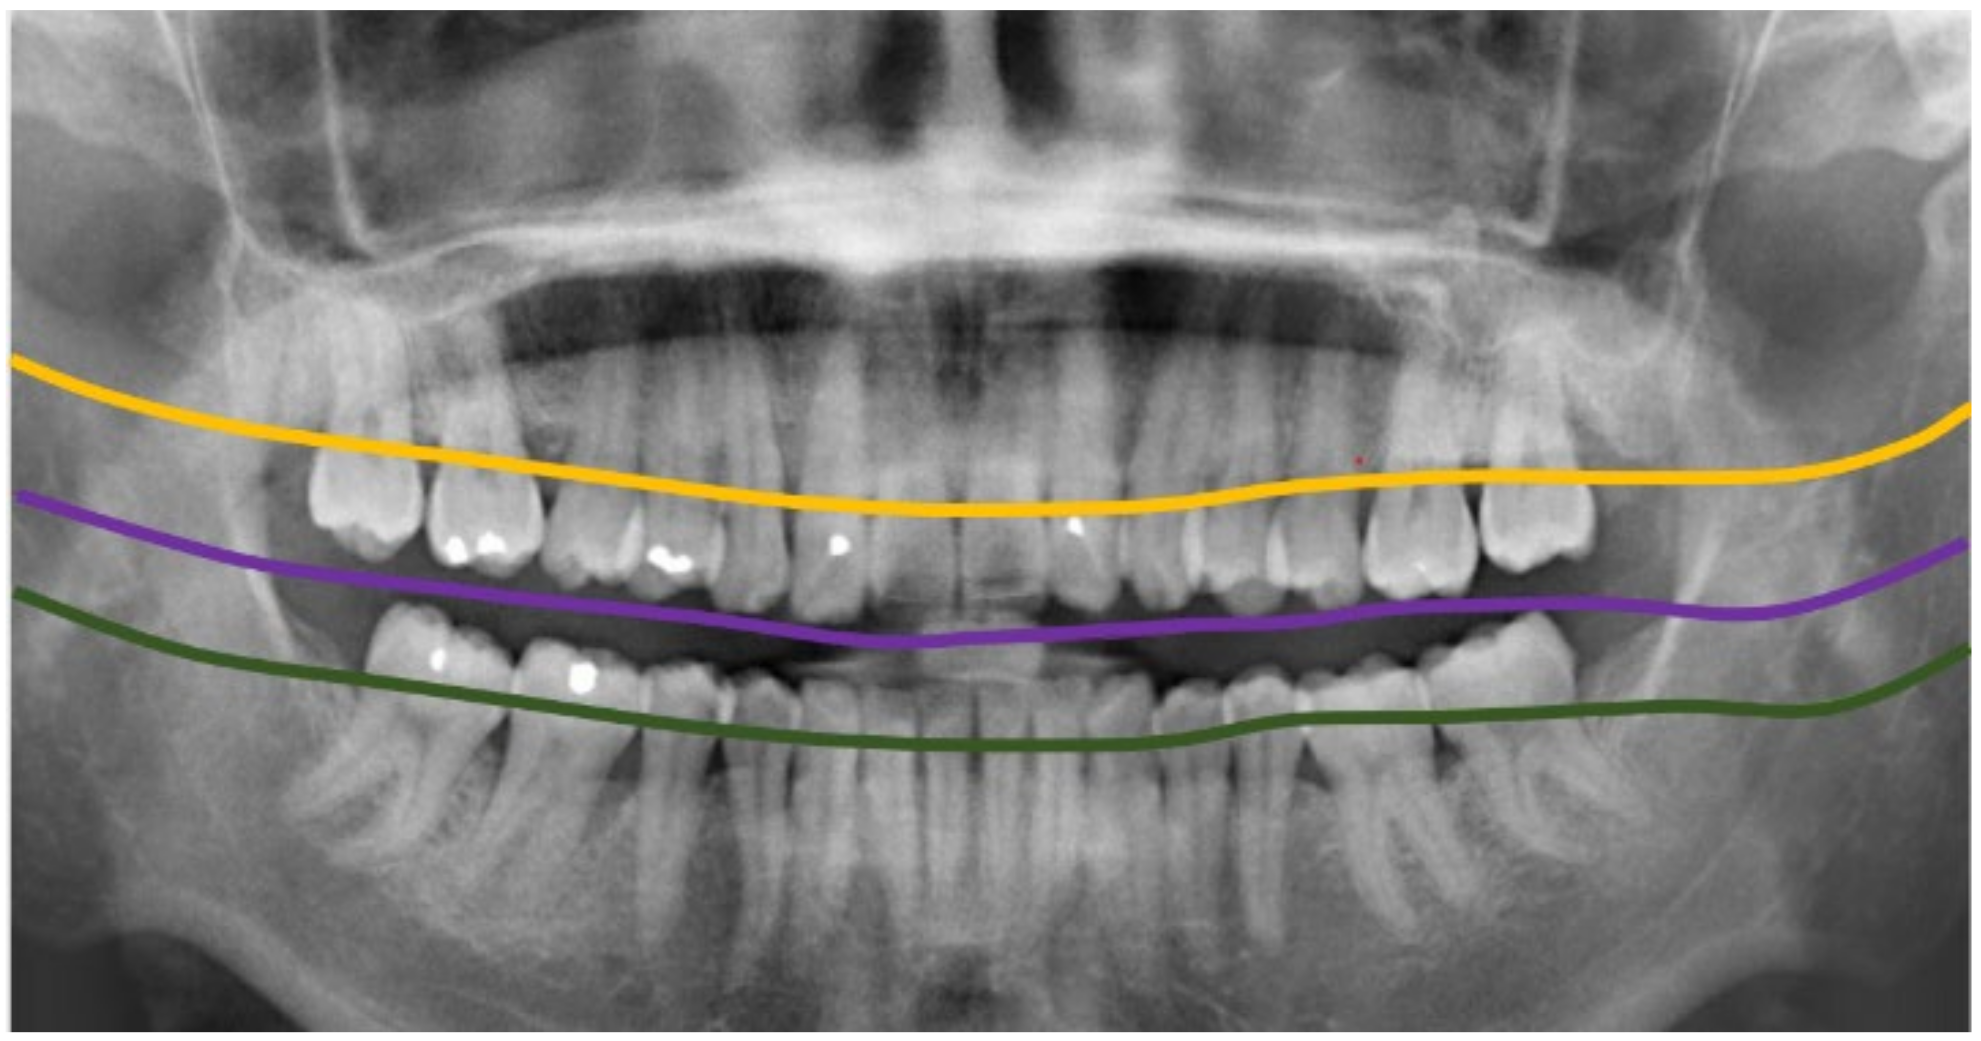

2.2.1. Curve of the Mouth

2.2.2. Curve Adjustment